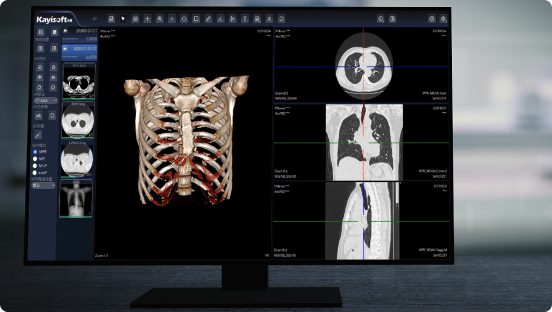

1、PACS软件架构:先进的全院PACS系统架构技术,轻终端模式,实现基于WEB架构的新一代PACS系统;

3、操作界面:人性化的界面布局设计,使操作变得简单,提高了可读性;

4、系统可深度集成第三方AI算法,获得AI分析结果,将AI分析结果在AI_PACS阅片页定位显示,坐标、病灶、分析等。医生在PACS中查看AI分析结果。

⚪临床调阅支持三维后处理